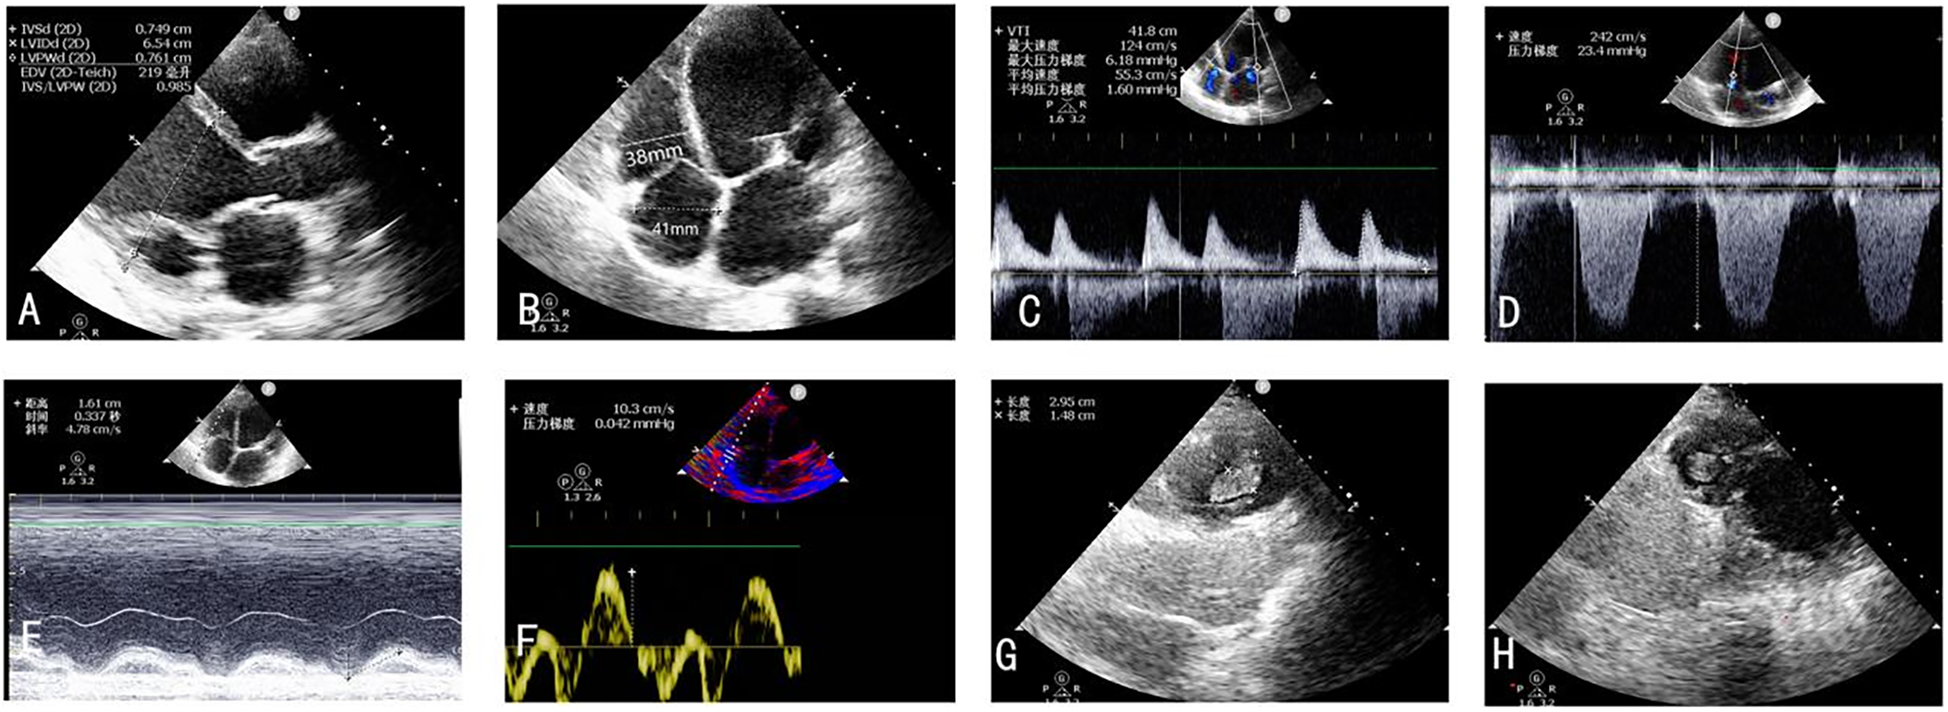

On postoperative day 2, repeat TTE demonstrated significant improvement in biventricular systolic function alongside favorable hemodynamic changes. Mitral regurgitation showed substantial reduction in severity, while tricuspid regurgitation exhibited marked improvement from severe to mild. Pulmonary artery systolic pressure decreased to 25 mm Hg from preoperative measurements of 45 mm Hg. Right ventricular remodeling was evidenced by decreased chamber dimensions following TEER. Right ventricular functional parameters demonstrated modest enhancement: TAPSE increased from 13 mm to 15 mm, while peak systolic tissue Doppler velocity (S′) remained stable at 9 cm/s (Figures 3A–D), and no right-to-left shunt was detected. Notably, echocardiographic evaluation revealed multiple apical thrombi within the right ventricular cavity (Figures 3E–G). Subsequent vascular Doppler studies of the lower extremities and pelvic vasculature demonstrated preserved triphasic flow patterns without evidence of deep venous thrombosis.

Figure 3

(A–F) TTE postoperative day 2 revealed significant improvement in biventricular systolic function alongside favorable hemodynamic changes. (G,H) Thrombus forming in the right ventricle on the second postoperative day.